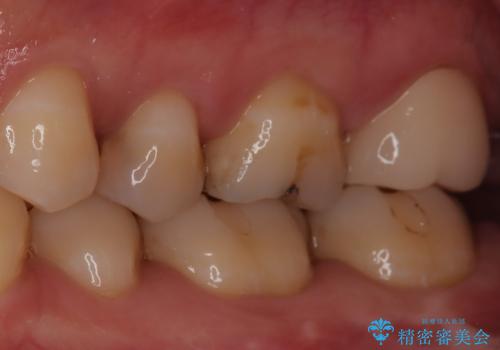

【精密根管治療】奥歯がズキズキ痛い。

- 奥歯がズキズキ痛いことを主訴に来院されました。

治療にて歯髄は保存できないと判断したため、根管治療を行いセラミッククラウンにて修復しております。